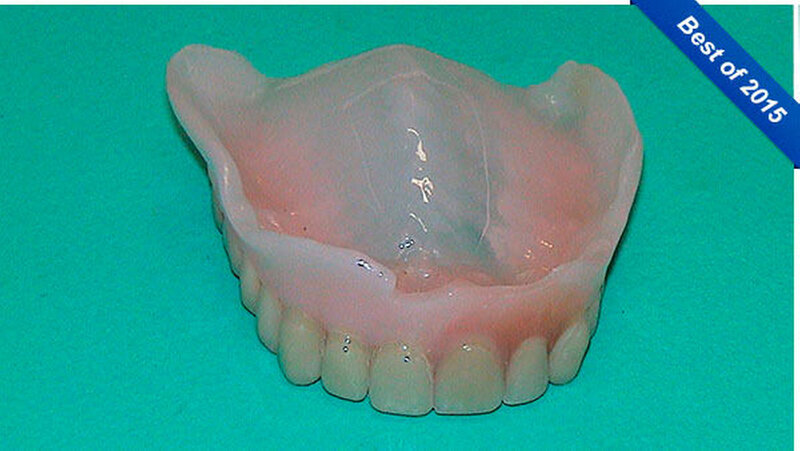

Er schreibt: "Als eine Patientin unsere Praxis aufsuchte, um sich im Notdienst ihre frakturierte totale Oberkieferprothese reparieren zu lassen, so war dies an sich noch kein spektakuläres Ereignis (Abbildung 1). Doch als sie gebeten wurde, auch ihre subtotale Unterkieferprothese mit Drahtklammerfixierung am teil-retinierten Zahn 47 zum Zwecke einer eingehenden Inspektion der Mundhöhle zu entfernen, reagierte sie merkwürdig zögerlich, unwillig und peinlich berührt. Erst nach eindringlicher Bitte gab sie nach und entfernte den Zahnersatz (Abbildung 2).

Es ergab sich ein absolut überraschendes und in dieser Form sicherlich einmaliges Bild: Sowohl im Ober- als auch im Unterkiefer befanden sich durchgebrochene, zum Teil gekippte Zähne, die topografisch nur schwer zuzuordnen waren und von dem eingegliederten Zahnersatz vollständig bedeckt wurden (Abbildungen 3 und 4).

Ein daraufhin angefertigtes OPG belegte den vorgefundenen Zustand auf beeindruckende Weise (Abbildung 5). Anamnestisch ließ sich keinerlei Erklärung über die Ursache und das Zustandekommen dieser merkwürdigen Situation finden. Die Patientin konnte oder wollte darüber keine Auskunft erteilen. Nachdem ihr der wiederhergestellte Zahnersatz ausgehändigt worden war, erschien die Patientin trotz Terminvergabe nicht wieder in unserer Praxis."